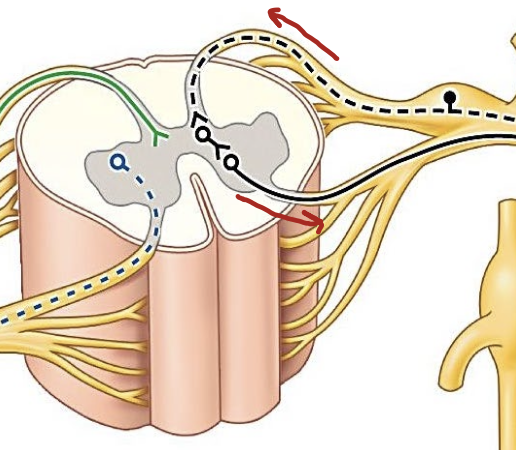

What is the teal line locating in this image?

Anterior Ramus; supplies anterior and lateral body wall

What is the green line locating in this image?

Posterior Ramus; supplies posterior body wall